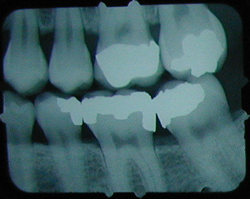

x-ray with cavity

Months later, cavities that start between the teeth can't be seen by visual examination, but they can be detected on an x-ray.

This cavity was detected and filled before the patient felt any discomfort, and before the nerve became infected or the tooth became abscessed.

There is another cavity shown in the X-ray on the right. Can you find it? It's difficult for the untrained eye to spot. Click here to see where it is. (Hint: It's not the left edge of the top left tooth. That's just the edge of the frame around the X-ray).